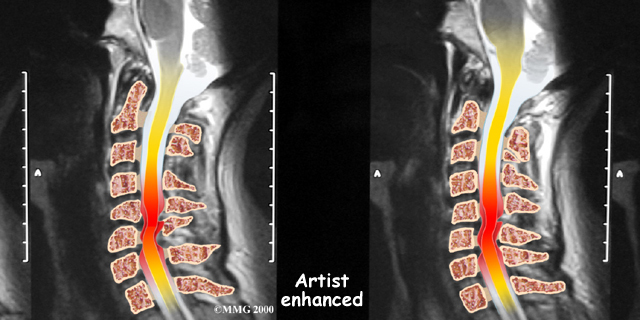

If more information is needed, your doctor may order a magnetic resonance imaging (MRI) scan. The MRI machine uses magnetic waves rather than X-rays to show the of the body. This test gives a clear picture of the spinal cord and can show where it is being squeezed. This machine creates pictures that look like slices of the area your doctor is interested in. The test does not require any special dye or a needle.

A computed tomography (CT) scan may also be ordered. The CT scan is a detailed X-ray that lets doctors see slices of bone tissue. The image can show if bone spurs are protruding into the spinal column and taking up space around the spinal cord.